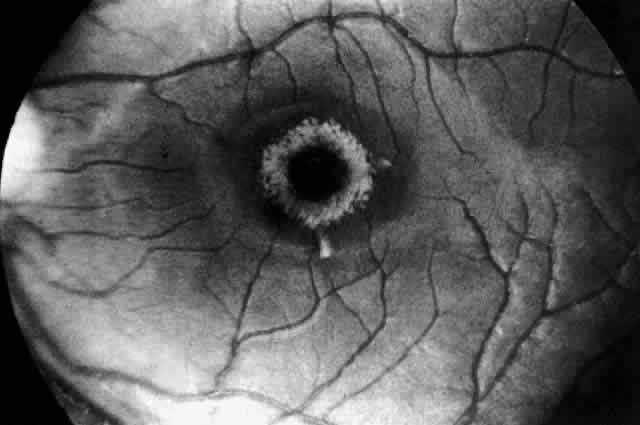

Electron microscopic examination of the cornea and retina showed the lipid stored was in the form of membranous cytoplasmic bodies (Fig. 7).68 The distribution of these inclusion bodies is similar to that of the birefringent material seen on light microscopy. The bodies are most abundant in retinal ganglion cells and retinal pigment epithelium. They are present in moderate numbers in corneal stromal cells, lens epithelium, corneal endothelium, vascular endothelium, and the sphincter muscle of the iris. They are infrequent in Müller cells, glial cells, and rod and cone inner segments.

Fig. 7. Retinal ganglion cell. (A) Portion of cell in Niemann-Pick disease, showing numerous membranous cytoplasmic bodies. Mitochondria (m) and dilated endoplasmic reticulum (er) are also evident. Area outlined in lower right is shown in greater magnification in B. (× 15,000) (B) Portion of cytoplasm of ganglion cell shown in A. Membranous cytoplasmic bodies cut in several different planes are evident, as are mitochondria (m) and endoplasmic reticulum (er) (×42,000). (Robb RM, Kuwabara T: The ocular pathology of type A Niemann-Pick disease: A light and electron microscopic study. Invest Ophthalmol 12:366, 1973)

The morphology of the membranous cytoplasmic bodies found in the eye in Niemann-Pick disease type A corresponds closely to the previously reported ultrastructure of lipid inclusions in the brain and viscera in other patients with Niemann-Pick disease type A. An ocular ultrastructural study of a 23-week-old fetus with Niemann-Pick disease type A also demonstrated rather extensive ocular involvement.69